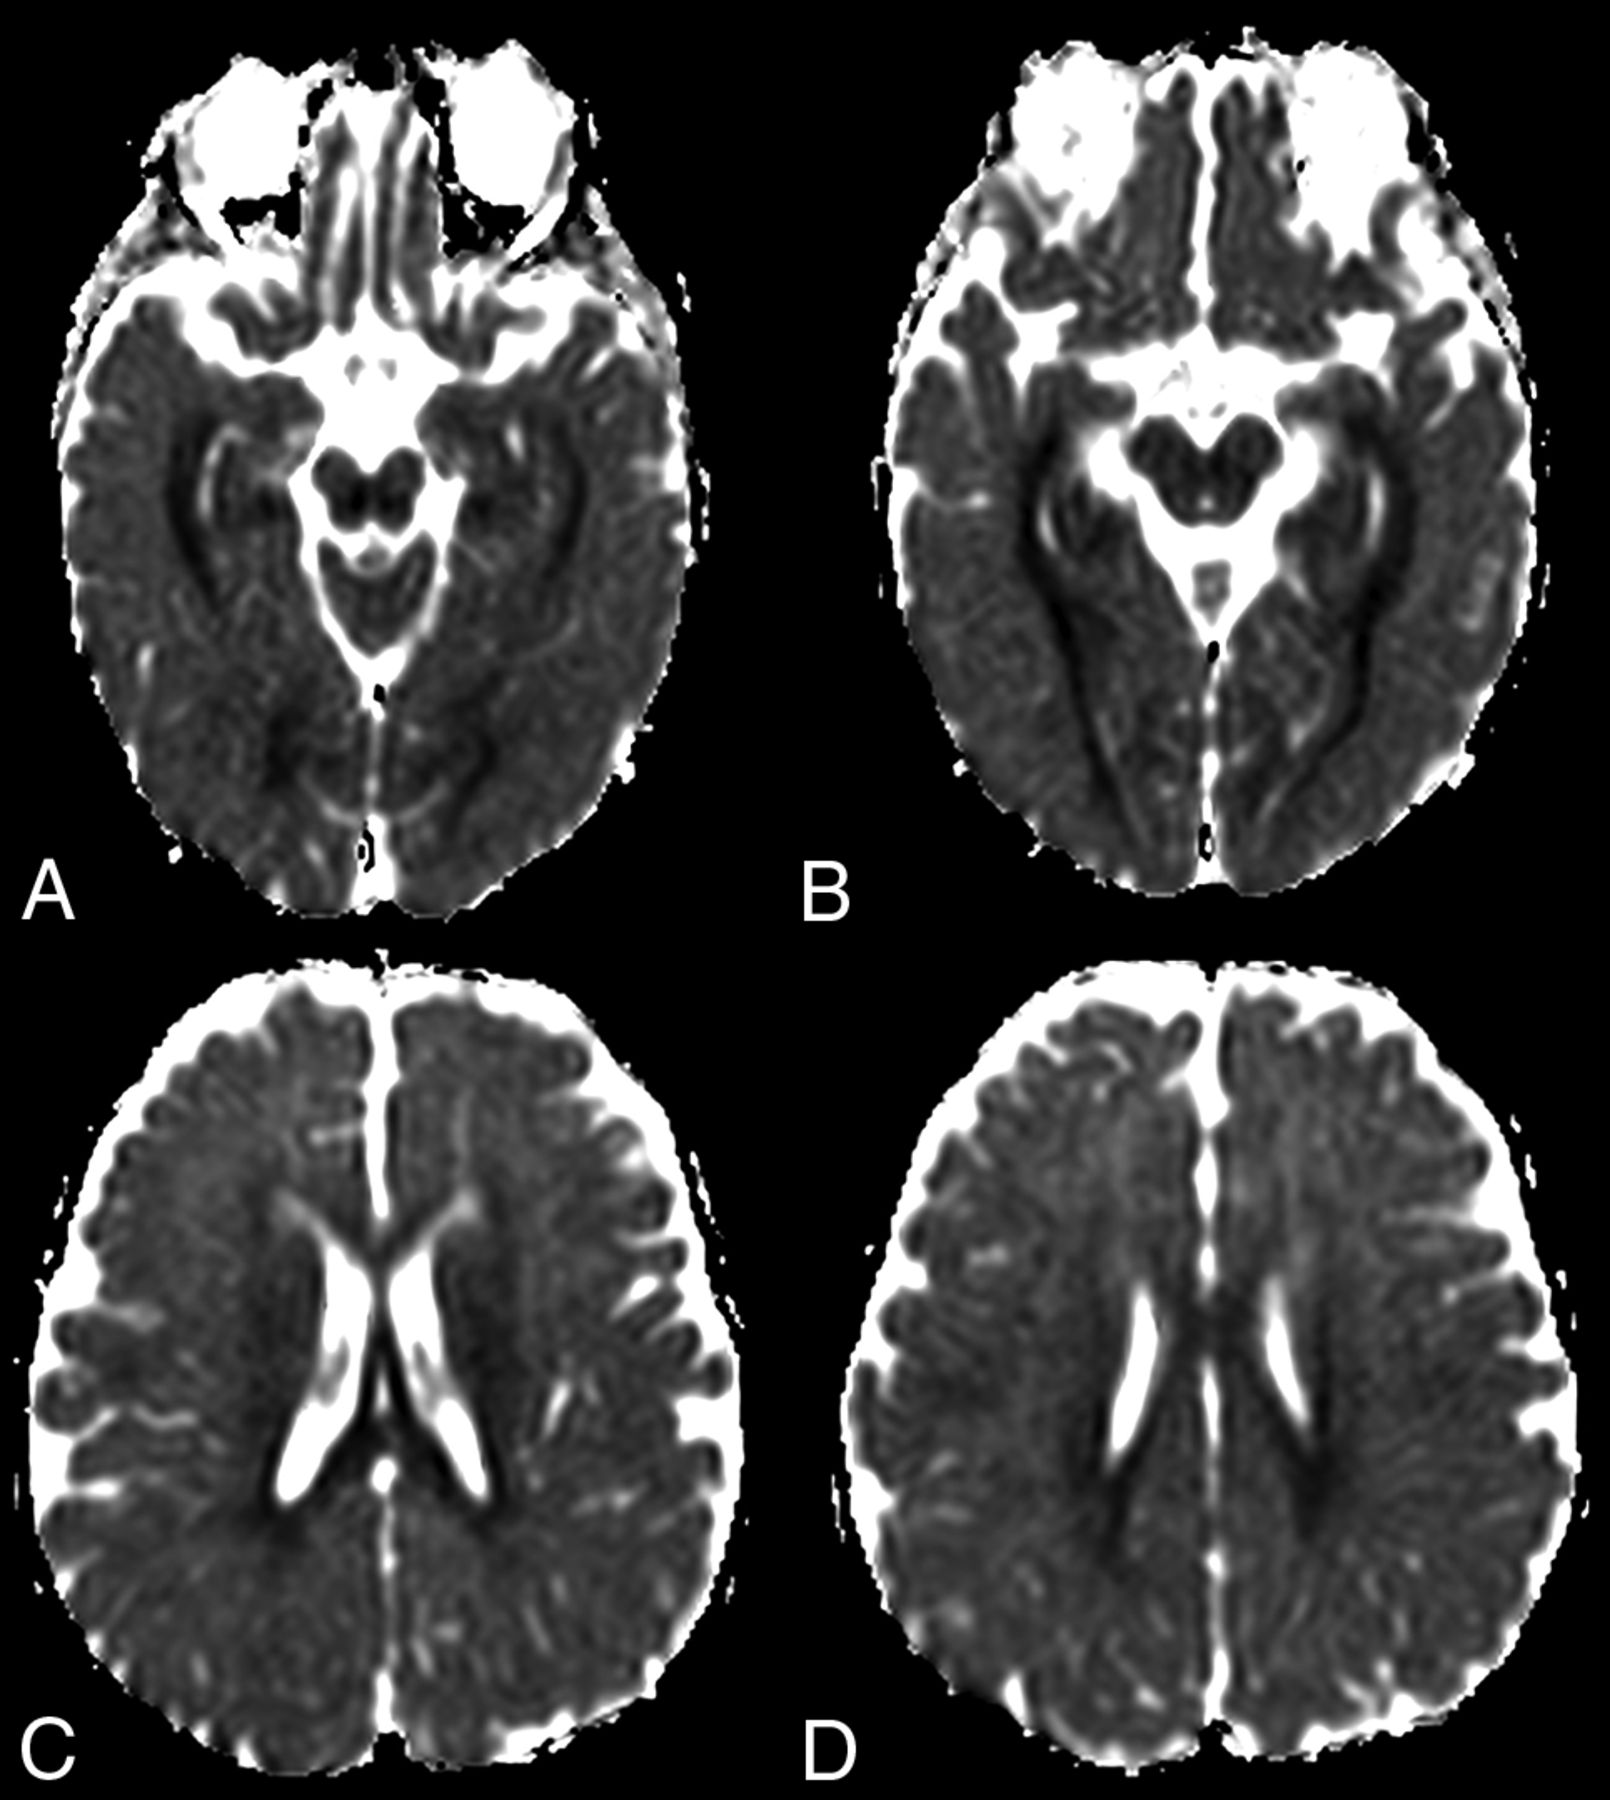

At diagnosis, brain MR imaging findings were abnormal in most patients (n = 12, 92%). The most common brain MR imaging findings were unilateral or bilateral perirolandic signal changes (n = 7, 54%) (Fig 1) and unilateral or bilateral thalamic signal changes (n = 10, 77%) (Fig 2). Perirolandic signal abnormalities were unilateral in most cases (n = 5, 71%) and were more frequently seen only affecting the precentral or both the pre- and postcentral gyri. Half of the thalamic changes were unilateral (n = 5, 50%). Simultaneous perirolandic and thalamic signal changes occurred in 6 patients (n = 6, 46%). An association of EPC (clinically/EEG) and perirolandic signal changes was present in 6 patients (n = 6, 75%), and an association of EPC (clinically/EEG) and thalamic signal changes, in 7 patients (n = 7, 87.5%). Two patients with EPC (clinically/EEG) did not present with perirolandic signal abnormalities. The findings positive for lesions overall were on the DWI of 10 patients (n = 10, 83%), on the T2WI of 9 patients (n = 9, 75%), and on FLAIR of 7 patients (n = 7, 58%). In 4 patients, DWI was the only sequence with abnormal findings. The occipital lobe was affected in the early brain MR imaging in 2 patients (n = 2, 15%). Signal changes in other brain regions were found in 5 patients (n = 5, 42%), involving multiple regions, namely the cerebral white matter, insula, putamen, caudate nucleus, fornix, cerebellar vermis, and also the frontal and occipital lobes. One patient did not present with either perirolandic or thalamic changes but instead presented with a diffuse pattern similar to that of leukoencephalopathy, with restricted diffusion in the white matter and white matter tracts (Fig 3). Three patients had an abnormally high lactate peak on MR spectroscopy. None of our patients had ASL or other perfusion-weighted imaging at the time of diagnosis. T1 and T2* imaging and SWI had negative findings at the time of diagnosis.

Perirolandic sign in 4 different patients with POLG-related disorders (A, An 8-month-old female), (B and C, A 3 year-old-male), (D, An 1-year-old male) and (E and F, A 9-month-old female). Signal changes around the central sulcus were variable with varying degrees of conspicuity. A, T2WI. Signal changes are subtle and focal, evident only in the left precentral gyrus (open arrows). B, T2WI. Signal changes are subtle and focal, evident in the left pre- and postcentral gyrus (open arrows), but more conspicuous in the DWI (open arrows, C). D, DWI. Linear signal changes involving mainly the cortex surrounding the right central sulcus (open arrows). E and F, DWI and ADC map, respectively. Marked signal changes in both right pre- and postcentral gyri.

The MR imaging appearance of the perirolandic sign was varied. Signal changes involved both the pre- and postcentral gyri, more commonly in the precentral gyri. The conspicuity of the perirolandic sign was also variable (Fig 1). In the more notable cases, signal changes were ribbon-like following the course of the gyri, which were readily detectable as T2 hyperintensities and restricted diffusion. DWI was the most sensitive MR imaging sequence to detect signal changes and, therefore, should always be included in the protocol and carefully evaluated when a case of POLG-RD is suspected.